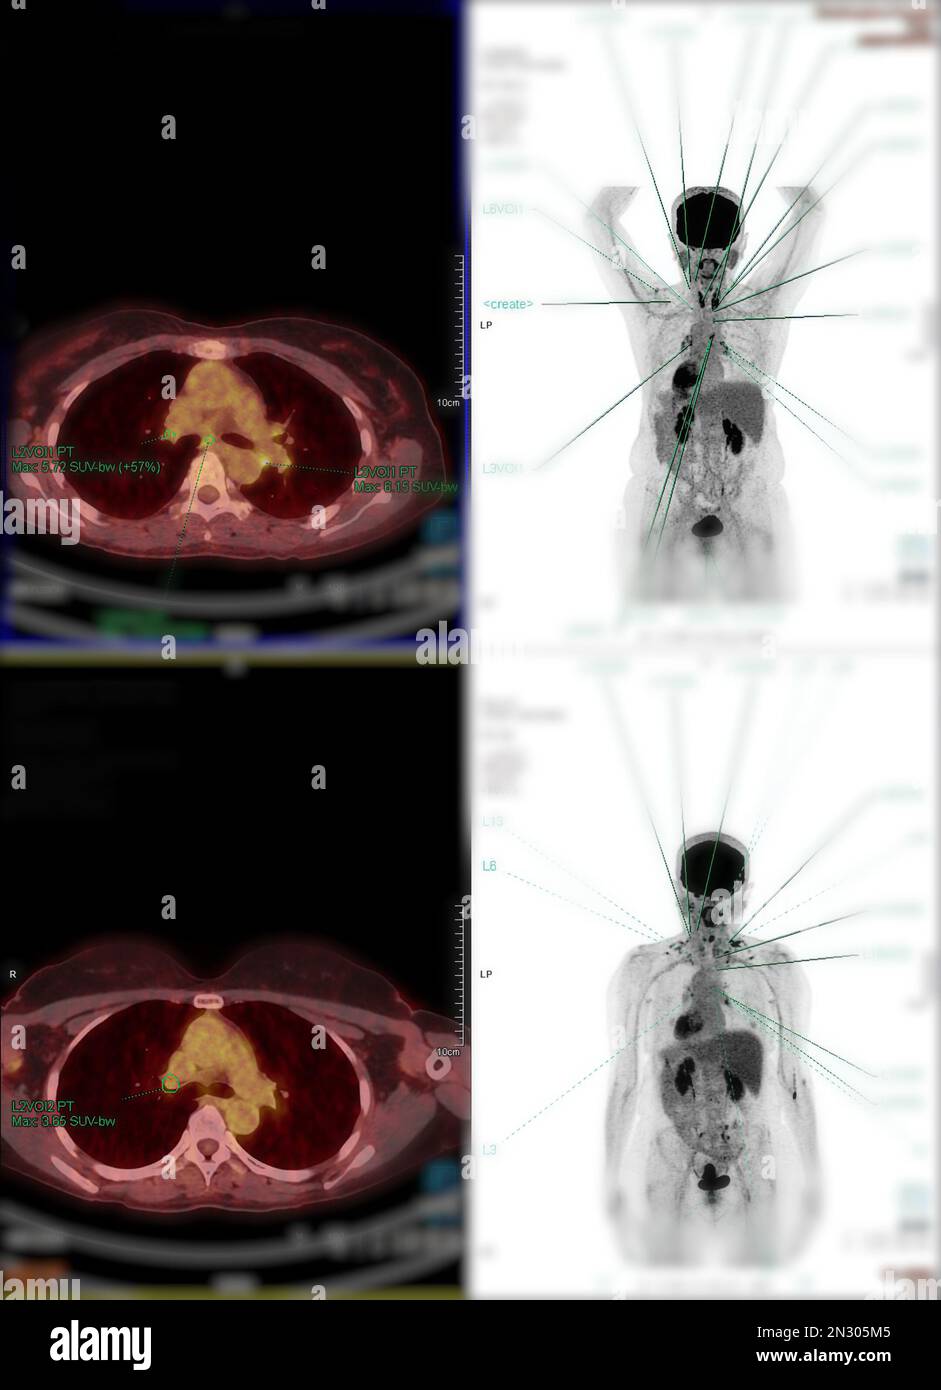

RF2N305M5–La tomographie par émission de positrons (TEP) CT scan utilise un médicament radioactif (traceur) pour montrer l'activité métabolique normale et anormale de tout le corps humain

RF2N305G8–La tomographie par émission de positrons (TEP) CT scan utilise un médicament radioactif (traceur) pour montrer l'activité métabolique normale et anormale de tout le corps humain

RF2N305A6–La tomographie par émission de positrons (TEP) CT scan utilise un médicament radioactif (traceur) pour montrer l'activité métabolique normale et anormale de tout le corps humain

RF2N305BY–La tomographie par émission de positrons (TEP) CT scan utilise un médicament radioactif (traceur) pour montrer l'activité métabolique normale et anormale de tout le corps humain

RF2N305A8–La tomographie par émission de positrons (TEP) CT scan utilise un médicament radioactif (traceur) pour montrer l'activité métabolique normale et anormale de tout le corps humain

RF2N305HW–La tomographie par émission de positrons (TEP) CT scan utilise un médicament radioactif (traceur) pour montrer l'activité métabolique normale et anormale de tout le corps humain

RF2N305M1–La tomographie par émission de positrons (TEP) CT scan utilise un médicament radioactif (traceur) pour montrer l'activité métabolique normale et anormale de tout le corps humain